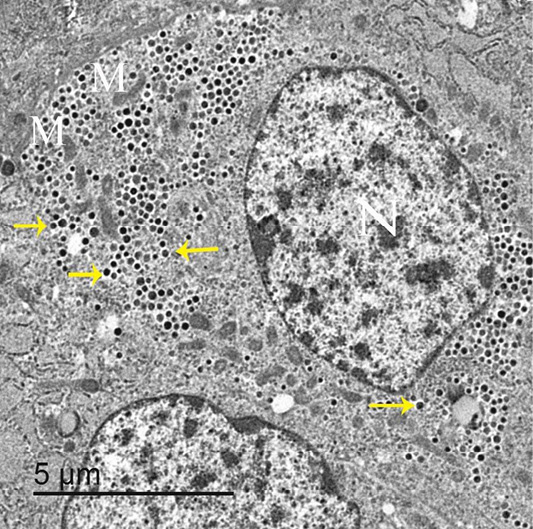

An electron micrograph of thyroid gland, showed that parafollicular cells had large and central nuclei “N”, elongated mitochondria “M” and darkly stained granules “arrows”.